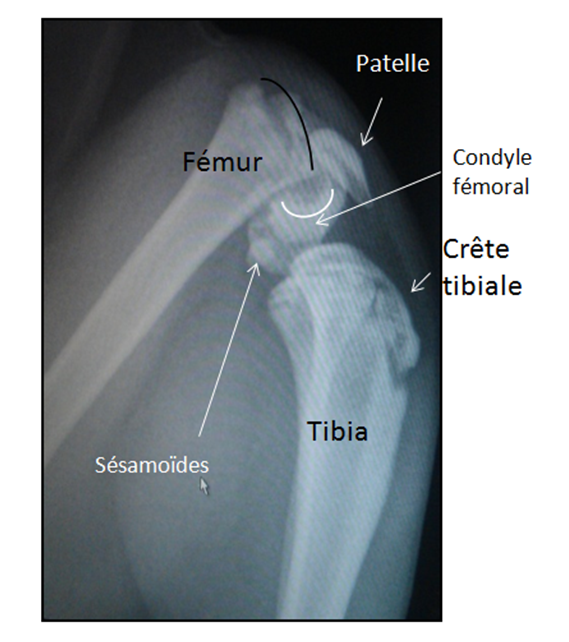

Je suis donc allée lui faire passer des radios chez le véto en pensant que c'était probablement de la dysplasie Mais, c'est bien pire que ça !Elle touche principalement les hanches, les genoux, les coudes ou la colonne vertébrale Comparateur Assurance Chat !La spondylarthrite ankylosante est une spondyloarthrite (maladie inflammatoire de la colonne vertébrale) atteignant surtout le bassin (sacroiliaque et hanches notamment) et la colonne

Libérer le Diaphragme #2 Détendre le muscle Psoas en position couchée Libérer le Diaphragme #3 Détendre les muscles inter omoplates Libérer le Diaphragme #4 Mobilisation Bonjour à Tous, Ci joint la radio de notre petite Lulu, chaton née le 17 Septembre 12 Quand nous l'avons eu, il était Ce dernier est dû à la présence d'un grand nombre de vaisseaux sanguins et lymphatiques dans les tissus pulmonaires Selon les résultats de l'autopsie, le cancer du poumon